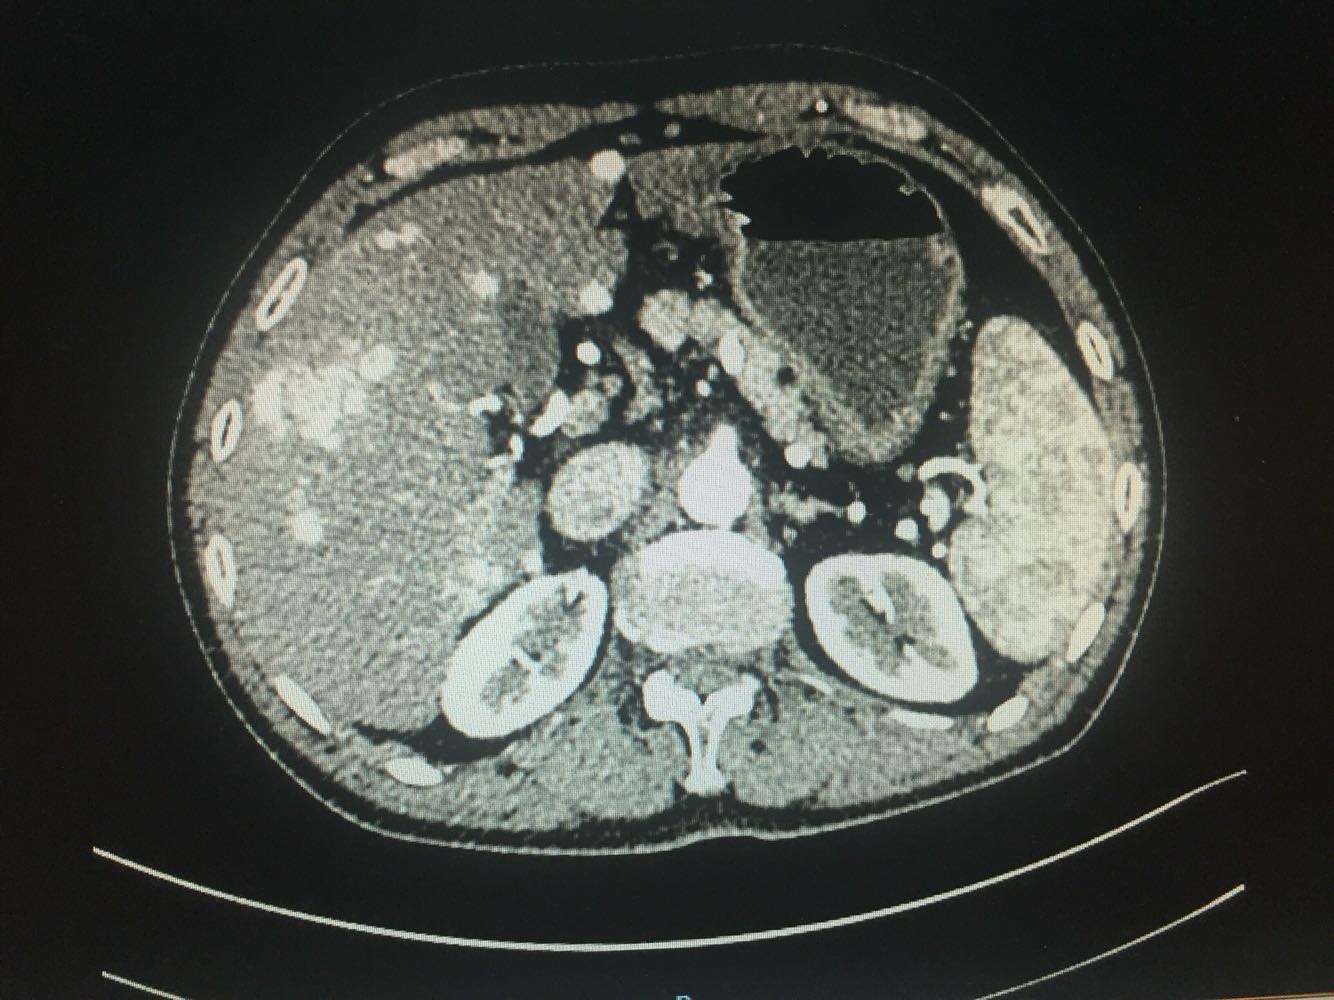

查体:体温,36摄氏度,脉搏:60次/分,呼吸,19次/分、血压,115/70mmhg,发育正常,营养欠佳,皮肤黏膜,色泽正常,双侧眼睑正常,双侧巩膜无黄染,口唇红润,双肺呼吸音清晰,心率60次/分,心律齐,心音有力,无病理性杂音。右上腹部饱满,中上腹压痛明显,肝脏肋下2cm触及,质地硬,触痛阳性,脾肋下2cm触及,移动性浊音阴性,肠音正常,双下肢无水肿 化验:血常规:白细胞计数2.9*10~9/L,中性粒细胞1.4*10~9L,红细胞计数4.03*10^12L,血小板计数76*10^9/L;生化全套。血糖4.67mol/L,总蛋白81.0g/L,白蛋白40.9g/1L,丙氯酸氨基转移酶256U/L,天门冬氨酸氨基转移酶182U,总胆红素22.0umol/L,胆碱酯酶4479U/L,Y-谷氨酰基转移酶137U/L;传染病9项:乙型肝炎病表面抗原阳性/6380,乙型肝炎病毒e抗体阳性/0.004,乙型肝炎病毒核心抗体阳性/0.008 肿瘤标志物:甲胎蛋白415.50ng/ml,乙型肝炎病毒DNA测定2.06E+07IU/ml CT:1.考虑肝右叶巨块型肝癌伴肝内多发转移,2.肝门部及腹膜后、心隔角旁小淋巴结。3.肝小囊肿。4.肝左叶増大。5.肝脏钙化灶。6.副牌。7.双肾微小囊肿

乙肝肝硬化,原发性肝癌,保肝抗病毒治疗,及TACE

出院一月后复查,行增强CT扫描,肿瘤明显缩小,肝功能正常,乙肝病毒复制转阴,建议继续口服恩替卡韦抗病毒治疗